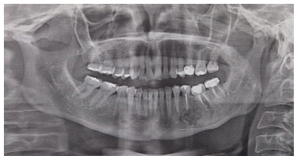

On 2006 A 47-year-old woman presented to the consultation and reported discomfort in the left mandibular area, in the panoramic x-ray a well-defined radiolucent area can be observed, apparently well encapsulated, which extends from the first premolar to the second molar with mobility grade one of the molars. An incisional biopsy was performed. The findings were semi-liquid content of yellowish, brown with pus content (Figure1).

Enucleation of the lesion and curettage of the area were performed, as well as a endodontic treatment of the second premolar, first and second lower left molar. The patient remained stable for 6 years when a panoramic rx was taken on 03/13/2012 as a control (Figure 2).